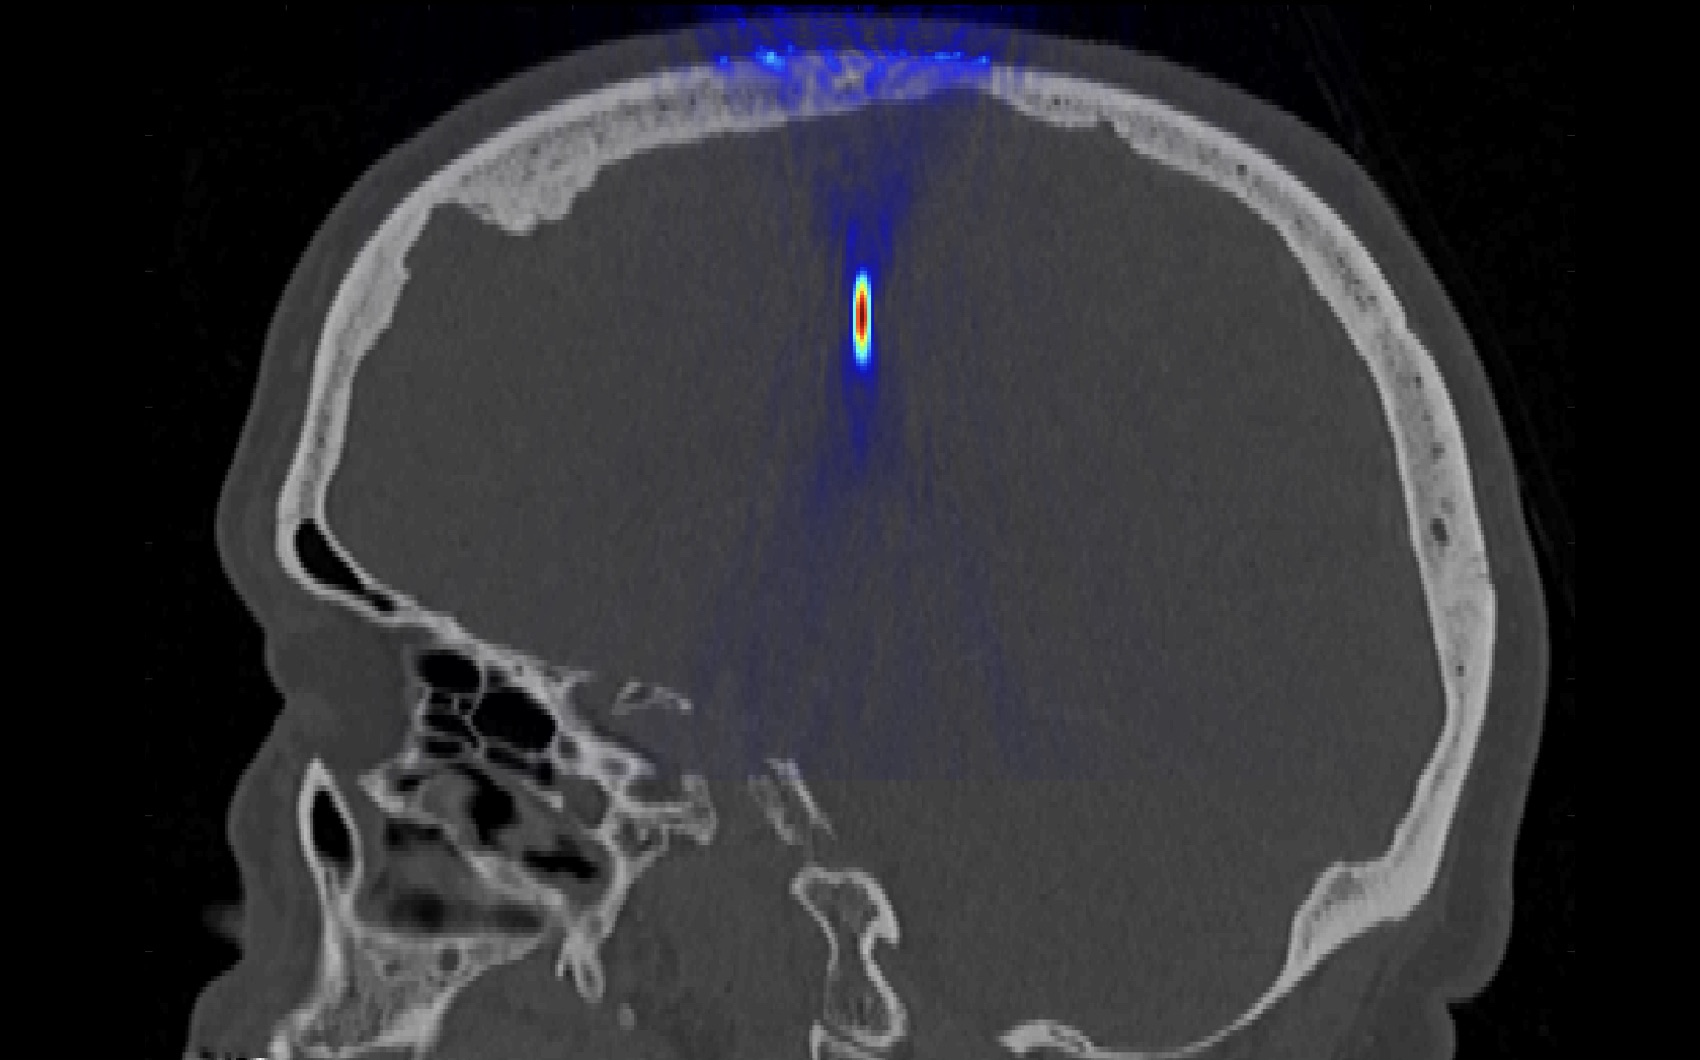

В существующей клинической системе HIFU (Insightec, Israel) планирование воздействия проводится на основе данных заранее проведенной компьютерной томографии (КТ), создания на ее основе акустической модели головы и моделирования фокусировки ультразвука в заданную область мозга с возможностью компенсации аберраций, вносимых неоднородной по толщине структурой костей черепа. При этом само облучение HIFU проводится под МРТ-контролем. Однако на данный момент существующие клинические системы позволяют воздействовать только на центральные области мозга, хотя причины многих заболеваний, в том числе и опухоли, часто локализованы в других областях мозга.

- сравниваются различные методы коррекции: лучевые, основанные на геометрической акустике, которые сегодня применяются в клинической системе, и новые дифракционные методы, позволяющие обеспечить качественную коррекцию в более широком диапазоне глубин фокусировки.

Конечной задачей является создание акустической модели головы человека для развития новых методов неинвазивной ультразвуковой хирургии с использованием нелинейных волн и фантомов черепа, сконструированных с помощью 3D печати.